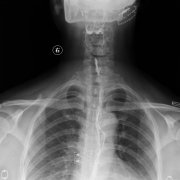

食管炎對(duì)于我們來說影響是非常大的,尤其是對(duì)平時(shí)的飲食,導(dǎo)致患者在吃東西的時(shí)候下咽疼痛,食管炎疾病是生活當(dāng)中的常見疾病,這樣的疾病給我們患者帶去的健康影響比較大,患有了食管...